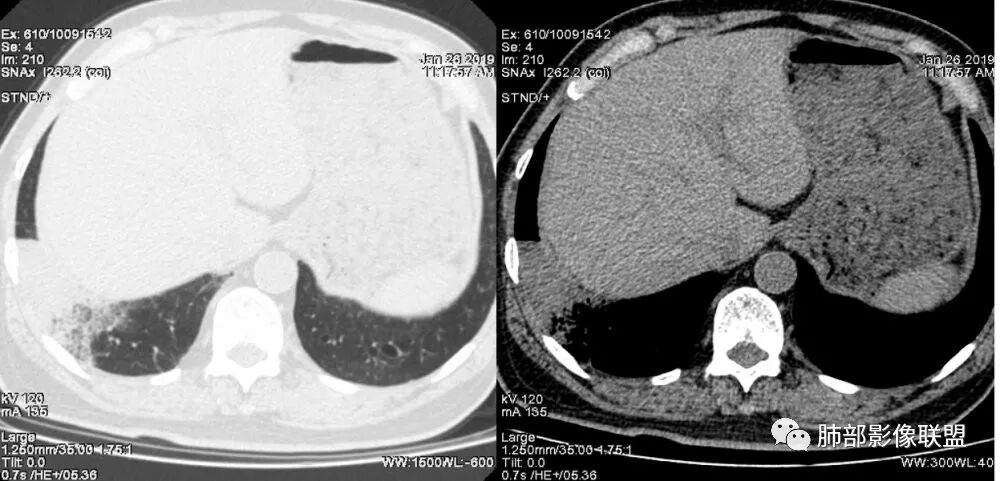

老年女性,右肺下叶沿胸膜下大片状高密度影,外周磨玻璃影,边界较清,内可见蜂窝征及支气管充气征,考虑肺炎型肺癌。

老年女性,咳嗽咳痰病史,右肺下叶大片磨玻璃实变影,胸膜下分布,支气管进入后扩张、僵直,磨玻璃影边界清楚,考虑粘液腺癌。鉴别肺炎。

右肺下叶基底段靠胸膜实变/磨玻璃混杂密度影,边界清楚,内见多发空泡(蜂窝样趋势改变?); 临床:咳嗽咳痰,无发热、胸痛; 考虑腺癌:无发热,感染性病变不首先考虑;部分层面形态类楔形,鉴别肺栓塞

老年女性,右下肺实变影,病灶里有小叶内间质增厚,周围GGo,支气管扩张,粘液性腺癌?淋巴瘤?

中年女性,咳嗽咳痰。右肺下叶片状高密度影,部分实性密度,周围见边界清晰磨玻璃影,内见小空泡,实性区部分支气管堵塞,有重力效应,考虑肺炎型肺癌,建议查痰脱落细胞。

老年人,右肺下叶斑片状阴影,病灶有膨胀性,边缘可见磨玻璃影,其边界清晰,内见僵硬的支气管,部分支气管扩张,首先考虑占位性病变,粘液性腺癌可能。鉴别感染性病变,后者边缘多有收缩性改变或者平直,内部支气管走形自然。

1.本例病灶较大片混杂密度影,胸膜下分布为主(未沿着支气管分布),该分布特点可见于大叶性肺炎、干酪性肺炎、淋巴瘤及粘液腺癌等。可惜未提供增强扫描图像。

2.病灶示中央实变区,周围GGO,可见明显小叶间隔增厚,GGO边界清楚,应当考虑到恶性病变的可能性。肺炎因炎性水肿及渗出,影像上边界常模糊不清,注意早期粘液腺癌可出现似清非清的边界。粘液腺癌因粘液成份较多,密度一般偏低,纵隔窗病灶常会消隐或范围会明显缩小,这不同于炎性实变。

3.病灶内支气管走形略显僵直,侧支少(粘液阻塞),也符合肺腺癌的枯树枝征。而大叶性肺炎的支气管是管壁光整、通畅、自然,结核的支气管常常壁增厚,甚至狭窄后扩张;